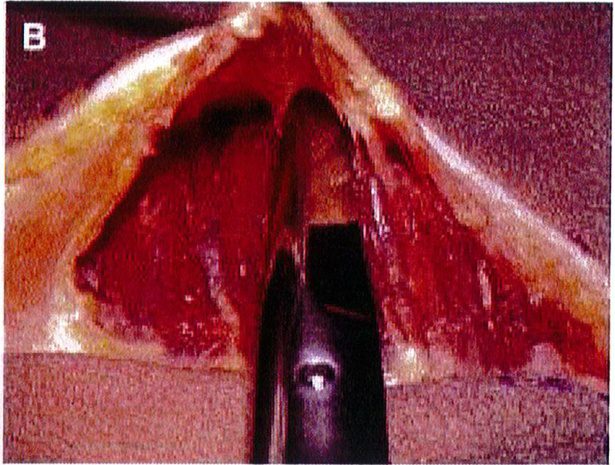

Hình. 3. (A) Lớp cân mạc che phủ cơ mông lớn. (B) Bóc tách lớp cân và cơ để tạo mặt phẳng cấy ghép. (Trích từ de la Pena JA, Rubio OV, Cano JP, et al. Subfascial Nâng mông. Clin Plast Surg 2006;33:409; đã xin phép trước khi đăng tải.)

Tiêm tê dưới da bằng hỗn hợp lidocain 2% với epinephrine sau đó thêm ropivacain 7.5%. Trên lỗ hậu môn 5cm, rạch hai đường mỗi đường dài 6cm về hai phía mông cho tới khi tiếp cận được lớp cân mạc ở bờ ngoài xương cùng. Từ vị trí đó, tiếp tục rạch một đường dài khoảng 8-10 cm song với bờ ngoài xương cùng, đi lên trên và cong lõm về phía mông tương ứng để bộc lộ lớp dưới cân (Hình 8).

Hình. 8. (A) Phẫu thuật được lên kế hoạch, sử dụng các tiêu bản phù hợp với vùng mông của bệnh nhân với các đường rạch dài 6cm ở hai bên, trên vị trí hậu môn ít nhất 5cm. (B) Đây là hình ảnh bệnh nhân với tiền sử có bệnh lý liên quan vùng mông, đồng thời đã từng thực hiện hút mỡ mông trước đó, nên chúng tôi quyết định đặt đường rạch cao hơn bình thường để tránh các biến chứng.

Hình. 9. Đánh dấu các mốc giải phẫu quan trọng. (A) Đường rạch cân cơ mông lớn bắt đầu từ bờ ngoài xương cùng (B) Bắt đầu bóc tách lớp cân từ đường rạch ban đầu (Trích từ de la Pena JA, Rubio OV, Cano JP, et al. Subfascial Gluteal aug- mentation. Clin Plast Surg 2006;33:411; đã xin phép trước khi đăng tải.)